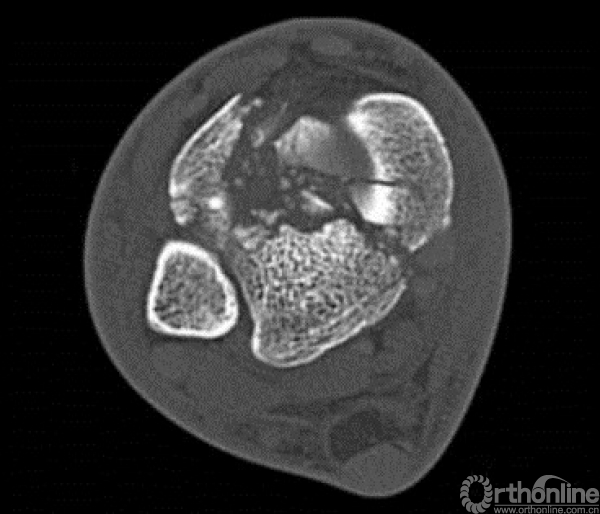

对于以下的骨折你怎么选择入路?

这样的骨折呢?